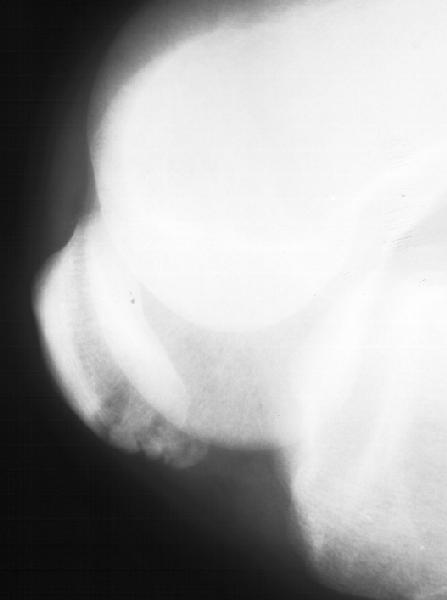

Мужчина 33 лет поступил через 2 недели после автоаварии (был за рулем) с переломом бедра. На этой же стороне есть перелом нижнего полюса надколенника. Клинически отека и гемартроза нет, интенсивная пальпация слабо болезненна прямо над линией перелома. Пальпаторно разгибательный аппарат сохранен. Бедро вчера синтезировано стержнем. Сделал сразу после этого снимок в полном сгибании - ничего никуда не расходится, и у меня рука не поднялась. Есть ли настоятельная необходимость оперативной фиксации, и если да, то чем?

since the fracture does not involve the articular surface and the q mechanism is intact, I agree you have done the right thing in not operating on it. As the fr is not displacing even in full flexion you may treat the patient as if e has no patellar fracture!

Остеосинтез бедра был 20.08.02, сегодня, 23.08.02, пациент пошел домой с одним костылем. Безболезненно сгибает колено до прямого угла (при

попытке согнуть дальше болит не колено, а передняя группа мышц в середине бедра), лежа свободно поднимает и удерживает на весу прямую

ногу. Со сгибанием до острого угла решили недели 2-3 подождать, и все.